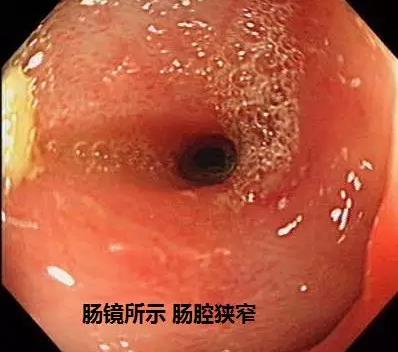

10年前,韩大姐由于发热、腹痛,在当地医院肠镜检查出“回盲部巨大溃疡”,并接受了“回盲部切除术”,术后证实为“克罗恩病”。之后反复腹痛、发热,辗转国内多家大医院诊疗,效果欠佳,只能依靠口服大剂量激素及抗生素维持治疗。1年前,韩大姐再次因克罗恩病并发肠穿孔、感染性休克,两次急诊接受“剖腹探查术+腹腔引流术”,从死亡线上将生命夺回,但腹壁窦道经久不愈,形成肠瘘,臭烘烘的粪便总是从腹壁瘘口中溢出,生活十分不便。于1月前来到郑州大学五附院胃肠外科就诊。

1.克罗恩病肠管节段性狭窄,多段梗阻,肠管粘连重,间隙脓肿常见,这导致其病变复杂,高复发率和再手术率。